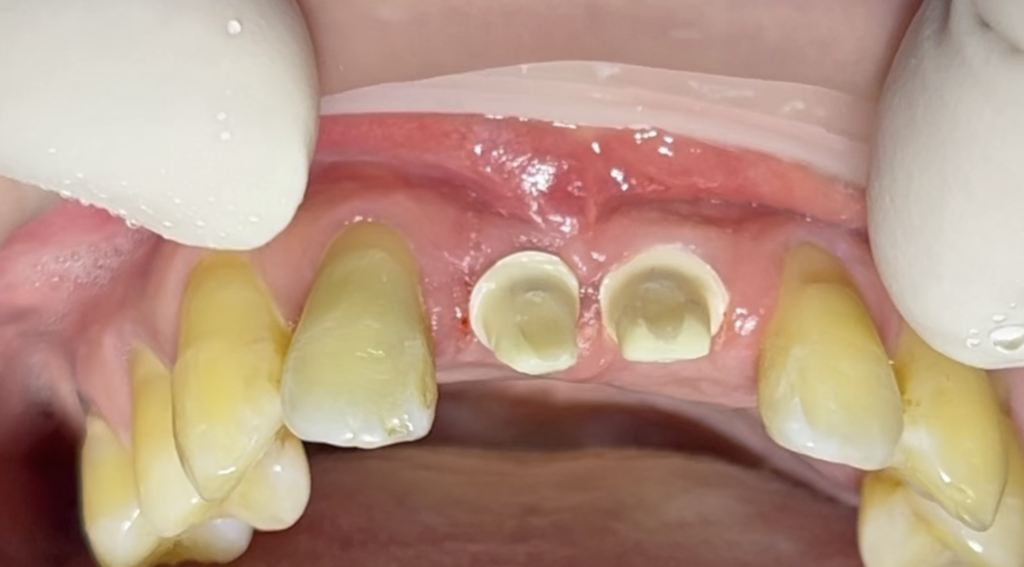

임플란트를 식립하고 설콘지대주를 연결한 모습

12번 탈구되어 재식립한 치아는 상태가 양호했지만 11번 21번 치근파절된 치아는 발치를 할 수 밖에 없었어요. 치근파절과 함께 뼈손상도 심해서 인공뼈와 인공막을 이용한 뼈이식을 하면서 앞니 2개 앵킬로스 임플란트로 식립후 설콘을 연결했습니다.